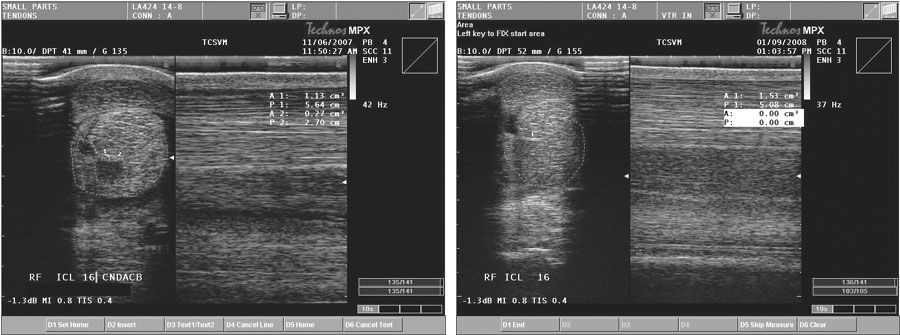

The Achilles tendon is the common calcaneal tendon and is most commonly injured by laceration in both dogs and cats.